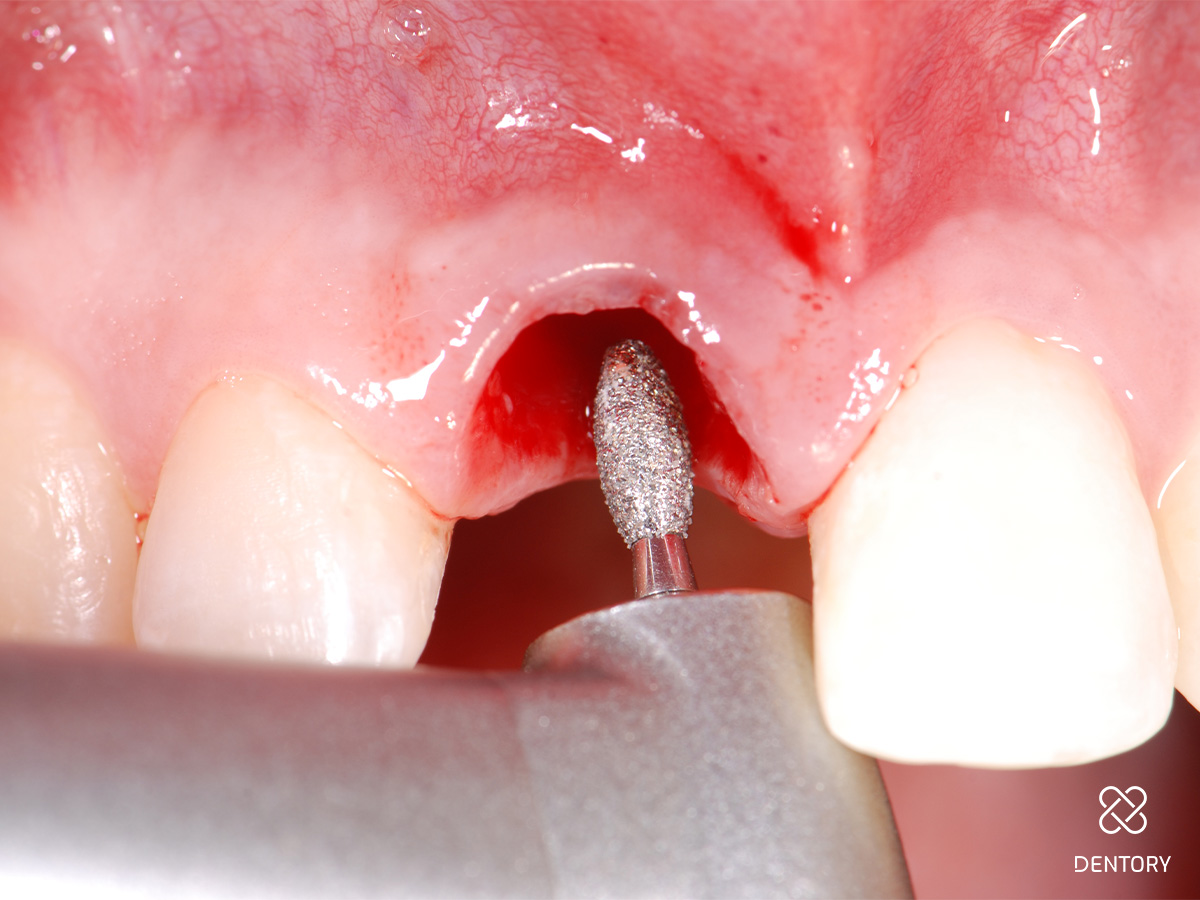

Abbildung 7

Sulkus deepithelialisieren: Voraussetzung für das Einheilen des Punches ist die Deepithelialisierung des Sulkus z.B. mit einem großen Diamanten.